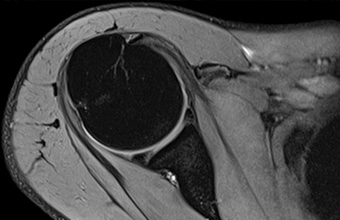

MR kostiju i zglobova

MR kostiju i zgobova (ortografija) posebno prilagođenim programom snimanja precizno oslikava povrijede kostiju i zglobova, odnosno njihove akutne i degeneratitivne bolesti.